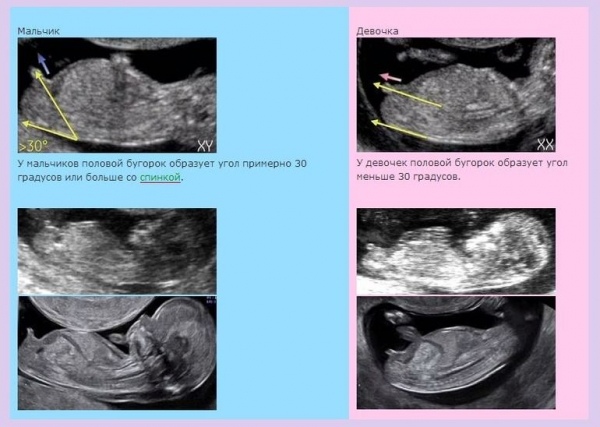

вот у нас тоже сына на первом скрининге увидели, хотя думали сестренка дочке будет. а потом наткнулась на эту картинку и решила пойти перепроверить)